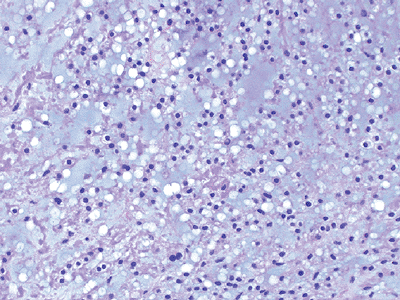

Diagnosis

Histologically characterized by nests of

tumor cells separated by sinusoidal vascular partitions, resulting in a

pseudoalveolar architecture (Fig. 12-15)

![]() |

|

Figure 12-15

Alveolar soft part sarcoma. Nests of tumor cells separated by sinusoidal vascular partitions resulting in a pseudoalveolar architecture. |